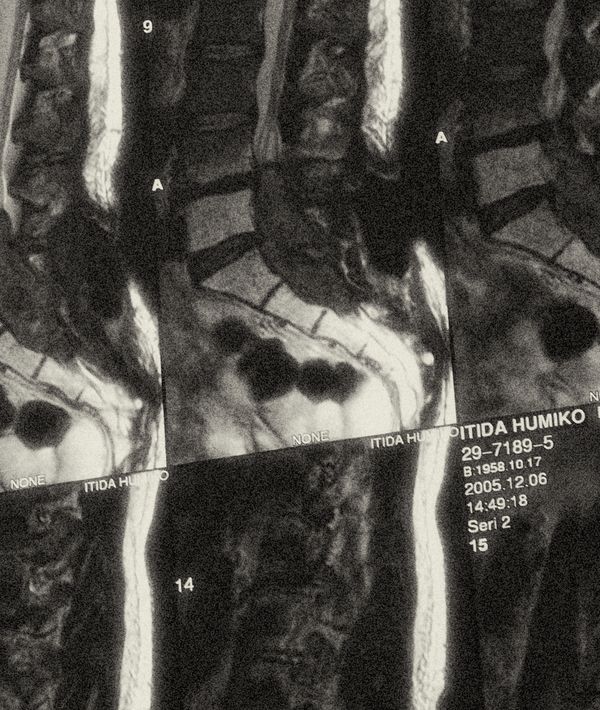

In 2006, my mother Fumiko died from lung cancer at the age of 47. I was in my last year of high school when she was first diagnosed, and she battled the illness for three years. Up to only a month before her death, I couldn’t conceive of the idea that she would succumb to cancer. I convinced myself that she would eventually defeat it, and be waiting at home for me again like before.

When my mom was healthy she was very self-critical and uncertain about herself, but when she was fighting her illness she was confident and determined to win. After she lost all of her hair from radiation and wore a wig for the first time, she made fun of herself and laughed very hard, even though my father, sister and I were very concerned about how it might affect her. It seemed that being sick allowed my mom to become more mentally strong. However, while she tried to be positive and tough, her physical strength deteriorated day by day. I slept with her in her hospital room for the last three weeks. As she started slipping in and out of consciousness, one day she suddenly sat up in bed and said in a clear tone: “How about Japanese pancakes for dinner tonight?” It looked like she didn’t understand that her own death was approaching.

I had my camera with me in the hospital room, as I thought I might want to capture something from my last days with her. But after seeing cancer completely change her appearance, I worried that photographing her in that state would erase my earlier, healthier memories of her. I barely managed to touch my camera in those final days.